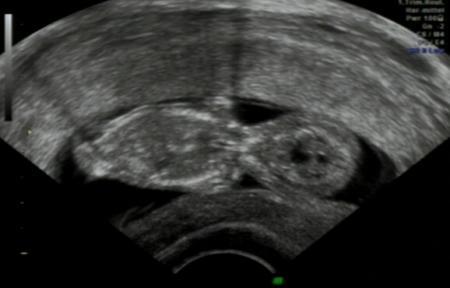

Ich hatte heute mein Erst Trimester Screening mit Nackenfaltenmessung und Blutabnahme. Ich weiß das viele hier dagegen sind, aber es war soooo toll und ich bin echt beruhigt! Nackenfalte ist 1,04 mm (ab 2mm ist bedenklich).

Es wurde ganze 20 Minuten Ultraschall gemacht und der Arzt hat uns jede Kleinigkeit gezeigt und erklärt. Das Krümelchen hat gezappelt wie verrückt und sich von allen Seiten gezeigt, hätte garnicht gedacht das die jetzt schon so aktiv sind Es ist jetzt 4,95cm groß ssl und hat einen Kopfdurchmesser von 1,72cm. Der Arzt meinte die kritische Zeit ist jetzt vorbei

laut Ultraschall Gerät bin ich 12+1 und nicht 11+1 aber wir warten erstmal ab bevor der ET geändert wird.

Ich versuche mal mein Ultraschall Bildchen anzuhängen